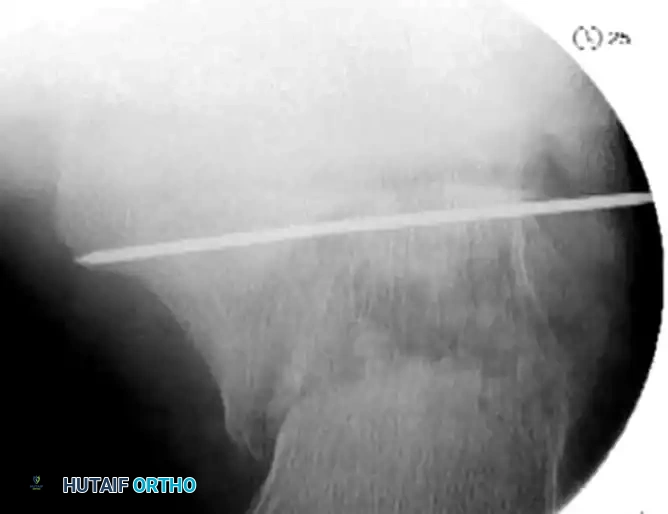

- Insert a large, fully threaded Steinmann pin or Schanz screw transversely into the posteroinferior aspect of the tuberosity fragment.

- Apply sustained manual traction in a plantar and valgus direction. This maneuver utilizes ligamentotaxis to disimpact the fracture fragments, restore calcaneal height, and correct the varus deformity.

- If manual traction is insufficient, a temporary external fixator or a femoral distractor can be applied between the calcaneal tuberosity and the distal tibia to maintain length and alignment during the procedure.